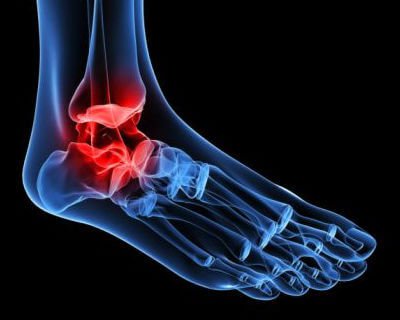

Den här typen av artros beror på varaktigt slit på brosket i fotleden. Det är vanligt att den blir stel och utvecklar deformiteter med åldern.

Klassiska osteofyter kan också uppkomma, vilket gör det till en väldigt smärtsam och begränsande åkomma.